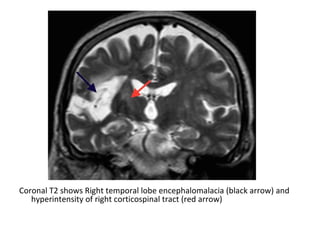

Coronal T2 shows Right temporal lobe encephalomalacia (black arrow) and

hyperintensity of right corticospinal tract (red arrow)